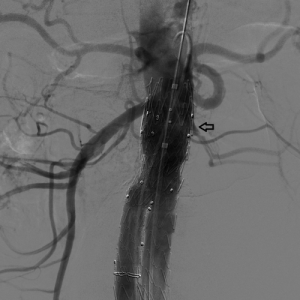

69 yaşında minimal invaziv kapak tamiri mümkün mü?

69 yaşındaki kadın hasta, posterior leaflet prolapsusu ve kord rüptürü nedeniyle ciddi mitral yetmezliği gelişmiş; akciğer ödemi ile yaşam kalitesi kritik seviyeye inmişti.

Minimal invaziv yöntem ile Carpentier tekniği, quadrangüler rezeksiyon ve ring implantasyonu yapılarak mitral kapak başarıyla tamir edildi.